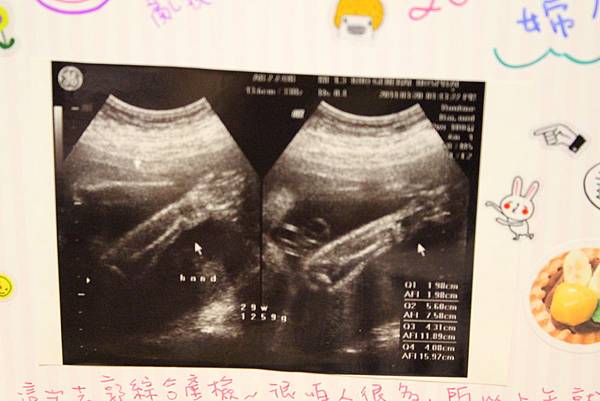

這次的超音波竟然只給我一張照片...

好少喔:(

然後這次的小Abby完全的把雙手遮住臉呀!

好像是突然換地方她好害羞這樣~

讓我跟醫生都覺得好可愛!